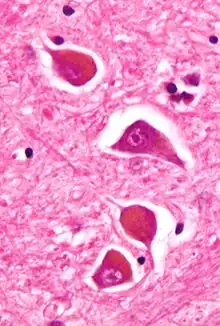

| Micrograph of Alzheimer type II astrocytes, as may be seen in hepatic encephalopathy. | |

There are various explanations why liver dysfunction or portosystemic shunting might lead to encephalopathy. In healthy subjects, nitrogen-containing compounds from the intestine, generated by gut bacteria from food, are transported by the portal vein to the liver, where 80–90% are metabolised through the urea cycle and/or excreted immediately. This process is impaired in all subtypes of hepatic encephalopathy, either because the hepatocytes (liver cells) are incapable of metabolising the waste products or because portal venous blood bypasses the liver through collateral circulation or a medically constructed shunt. Nitrogenous waste products accumulate in the systemic circulation (hence the older term "portosystemic encephalopathy"). The most important waste product is ammonia (NH3). This small molecule crosses the blood–brain barrier and is absorbed and metabolised by the astrocytes, a population of cells in the brain that constitutes 30% of the cerebral cortex. Astrocytes use ammonia when synthesising glutamine from glutamate. The increased levels of glutamine lead to an increase in osmotic pressure in the astrocytes, which become swollen. There is increased activity of the inhibitory γ-aminobutyric acid (GABA) system, and the energy supply to other brain cells is decreased. This can be thought of as an example of brain edema of the "cytotoxic" type.[12]